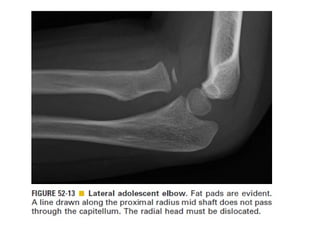

Skeletal trauma was presented by Dr Laith Fadhel with reference to Grainger's Diagnostic Radiology textbook. The presentation covered skeletal trauma as assessed through diagnostic radiology techniques. Key findings and treatments for skeletal injuries were likely discussed.